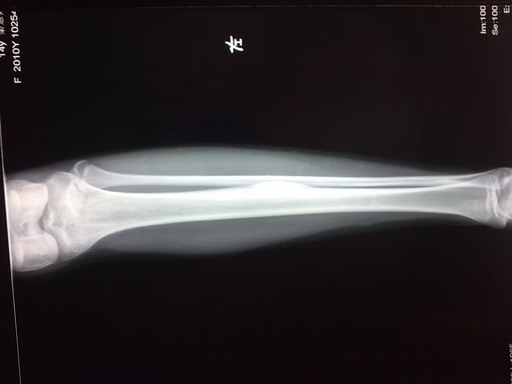

女孩,14岁,小腿疼痛一周,局部隆起,质硬,无红肿热痛

你侧胫骨中段见块状骨性突起。边缘清,并见硬化。考虑骨软骨瘤。

胫骨骨干皮质梭形增厚,虽无瘤巢,也考虑骨样骨瘤,原因不明,可能与感染有关,服用水杨酸制剂看看。

鉴别:骨化性纤维瘤、骨瘤、慢性骨膜下脓肿。

左胫骨中段内前方骨皮质梭形增厚,髓腔未见累及,无骨膜反应。考虑良性病变。我考虑1低毒感染。

2骨样骨瘤:骨硬化较重,可能包埋了“瘤巢”。不象的地方就是病史不太支持:病程比较短,症状比较轻。试服用水杨酸制剂看看。

考虑骨样骨瘤。病灶内部结构显示不清,请调调ct窗宽窗位。